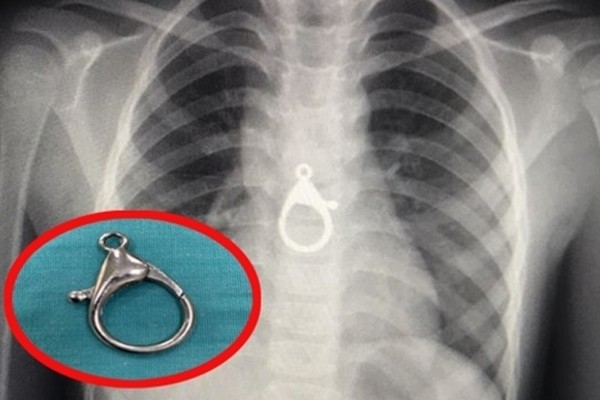

Trong lúc chơi, bé trai ở Quảng Nam đã nuốt chiếc móc khóa xe vào bụng, phải nhập viện cấp cứu trong tình trạng đau tức ngực, khó thở.

Tối nay (13/8), bác sĩ Nguyễn Thanh Tiên, Trưởng khoa Tai Mũi Họng (BV Đa khoa Quảng Nam), cho biết, vừa gắp thành công chiếc móc khóa ra khỏi thực quản bé trai 6 tuổi.

Móc khoá nằm bên trong ngực cháu H.

Theo đó, chiều nay, cháu T.Đ.H. (trú tại xã Tam Hòa, huyện Núi Thành, Quảng Nam) được đưa vào cấp cứu tại BV Đa khoa Quảng Nam, trong tình trạng đau tức ngực, khó thở.

Qua thăm khám và tiến hành chụp X-quang, các bác sĩ phát hiện dị vật ở vùng ngực đoạn D6-7-8 của H.

Bệnh nhân sau đó được chuyển vào Khoa Gây mê phẫu thuật. Tại đây, bác sĩ Tiên cùng ê-kíp đã nội soi và gắp thành công móc khóa ra ngoài.

Theo người thân, trong lúc chơi tại nhà, cháu H. ngậm móc khóa xe vào miệng, rồi nuốt vào bụng.

Chiếc móc khoá được gắp ra ngoài